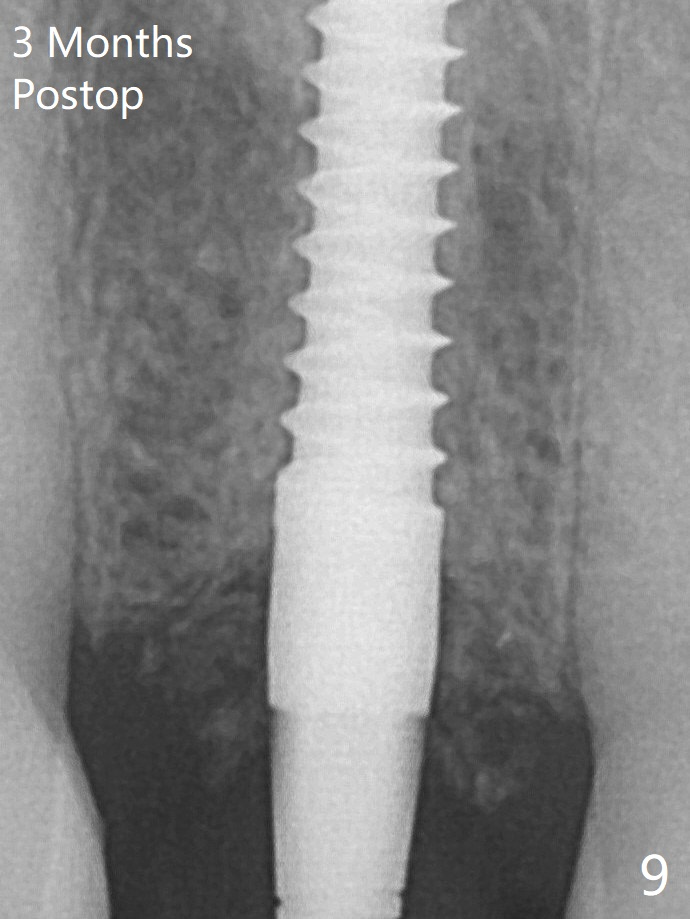

After adjustment of the trajectory of osteotomy (Fig.5), a 3x16(2) mm 1-piece implant is placed within normal limit (10-15 Ncm, Fig.6)).  In fact bone graft is placed before (^ arrowhead; to repair apical buccal plate perforation) and after (*) implantation.  The bone graft becomes more organized 3 months postop (Fig.9).术后三个月骨粉形态改变(图九,与图六对比)。